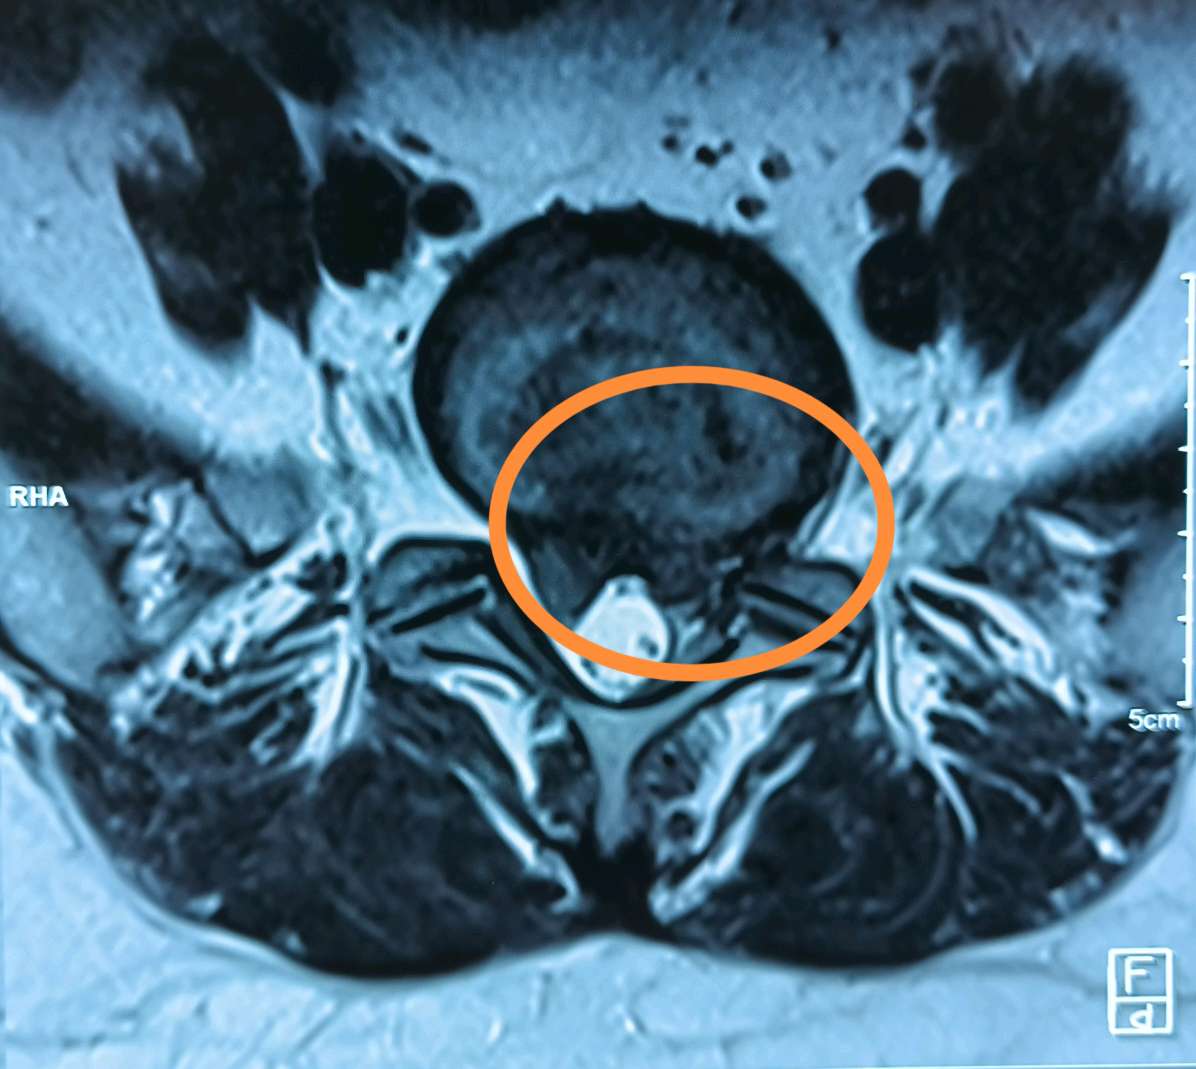

经检查,腰5/骶1右侧巨大突出,右侧骶1神经受压明显,患者不想手术,保守治疗几天,越治越重,不得已,只能接受微创手术!